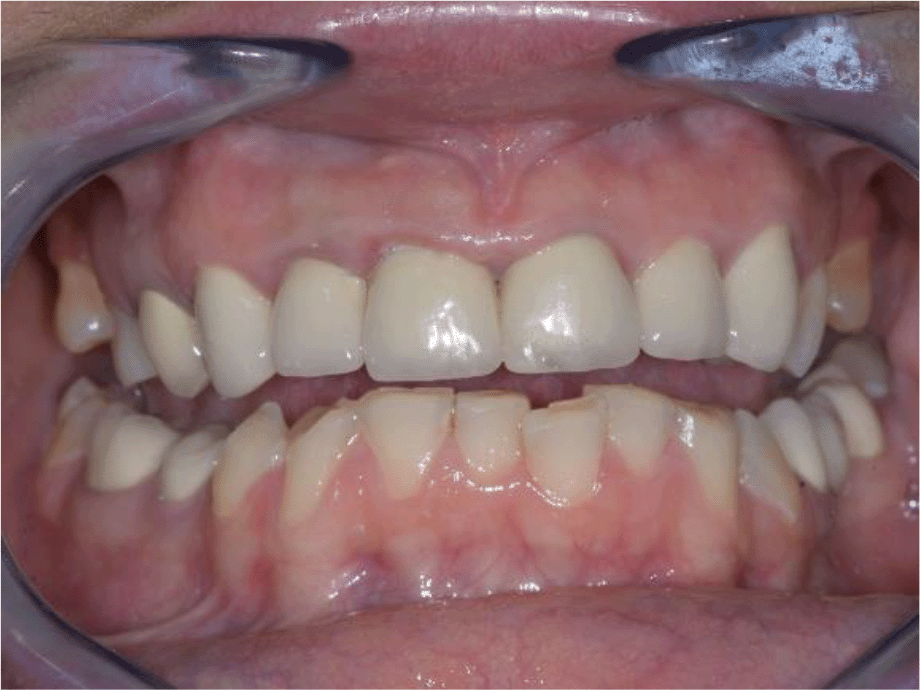

A 35-year-old female patient, Bulgarian restaurant owner, sought help due to impaired aesthetics, as a result of abraded tooth surfaces and severe symptoms of the right TMJ.

Intraoral examination of the upper jaw revealed a metal-ceramic construction on 13, 12, 11, 21, 22, 23, 24, missing 18, 16, 25, 26. The metal-ceramic construction was made 13 years ago, and was in good condition except for small fractures of the ceramic on the palatal surface and palatal staining of the gingiva by the metal base. The distal available teeth were medialized (Figures 1 and 2).

On the lower jaw, an advanced phase of abrasion (Attritio dentis cum abrasione) of the frontal teeth was established, reaching the dentin area. Defects of the dentitions were solved with ceramic restorations of 35, 36, 37 on the left and 45, 46 on the right. The occlusal plane was incorrect – the lower frontal teeth were higher. There was a deep overlap of the lower frontal teeth in central occlusion (Figures 3 and 4).

During palpation of the TMJ, the patient responded with mild pain on the right side.